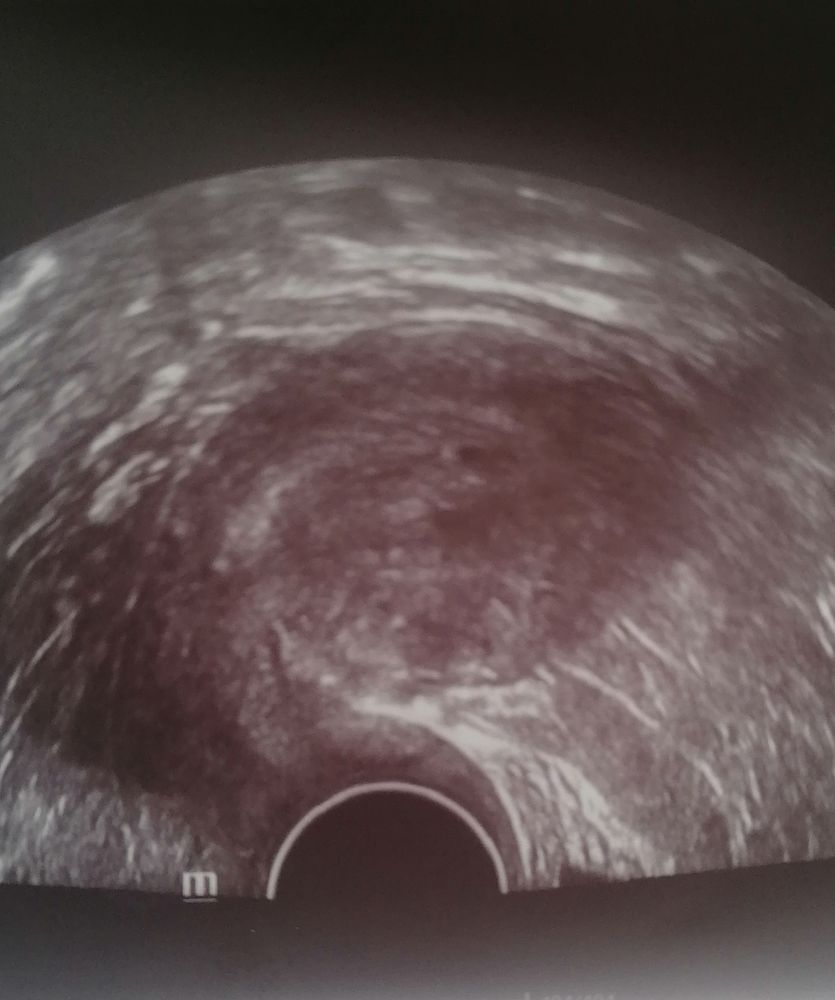

Вроде 2.

Вижу 2ПЯ

А что вам написали в заключении? Так рано еще совсем. Через неделю будет виднее) одно я вроде точно вижу. Второе - тут непонятно, узи такое дело, все в пятнах, тем более на таком сроке.

Ранний срок, плохо видно, мы не узисты. Вы были у врача, а мы должны угадать.